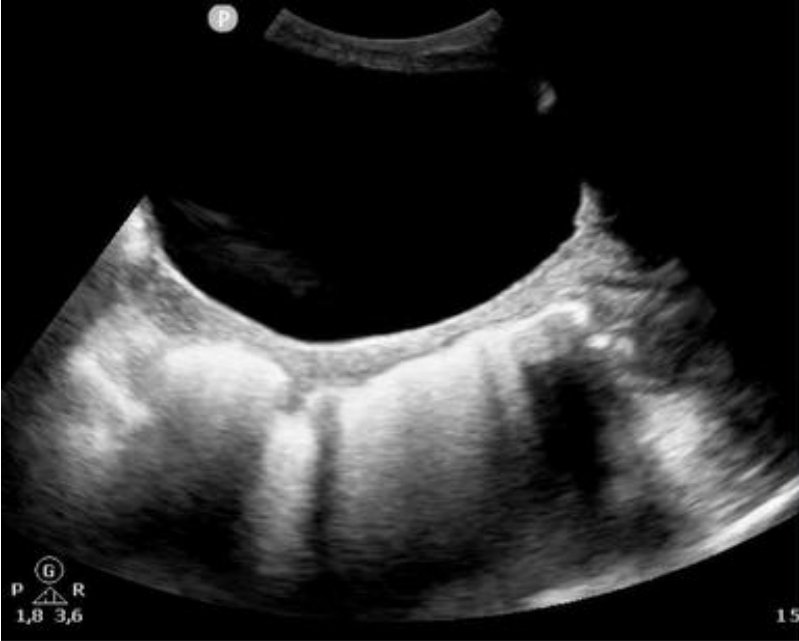

@DrStarWolf @ChampoDr @duran_georg @132_dc @DrGroquik Sans problème, c'est archi-débile. Se et VPN proche de 100%, permet de surseoir au TR. En transversal et longitudinal : image hyperéchogene colique rétro-vésicale avec cône d'ombre post, lignes B possibles si un peu d'air.

TheFrenchPOCUS tweet mediaTheFrenchPOCUS tweet media